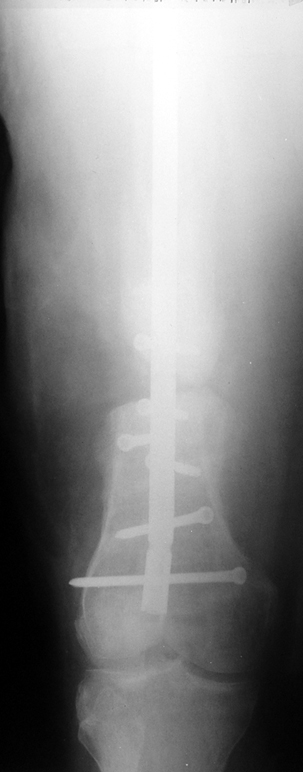

Eksternal fiksatör ile geçen süre (eksternal fiksasyon indeksi), gereken distraksiyon miktarına bağlıdır ve bu süre boyunca bazı komplikasyonlarla karşılaşılabilir. Distraksiyon dönemi sona erdikten sonra, distraksiyon süresinin iki katını aşan konsolidasyon döneminde hastalar eksternal fiksatörü zorlukla tolere edebilirler. Yeterli konsolidasyon sağlanmadan eksternal fiksatör çıkartılırsa ise kırıklar, deformite ve kısalık oluşabilir. Hastanın fiksatör ile birlikte geçirdiği sürenin azaltılması ve böylece hasta konforunun ve aktivite düzeyinin arttırılması için intramedüller çivi üzerinden uzatma yöntemi uygulanmaktadır. Bu yöntemde distraksiyon dönemi sona erdiğinde kemiğin içindeki çivi statik olarak kilitlenmekte ve eksternal fiksatör çıkartılmaktadır. Stabilizasyon intramedüller çivi tarafından sağlandıktan sonra konsolidasyon dönemi gerçekleşmektedir. Bu şekilde hem eksternal fiksatörün uzun süre kalmasından hem de erken çıkartılmasından kaynaklanan komplikasyonların önüne geçilmektedir.

Vaka 1